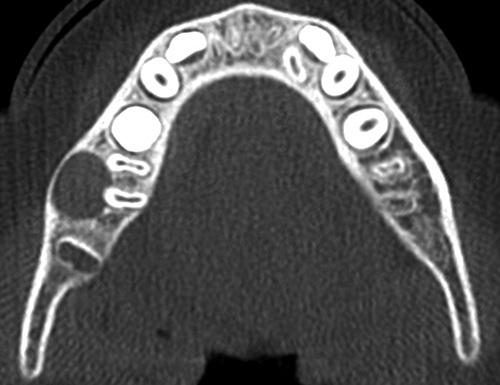

Axial computed tomography (CT) image showing a circumscribed radiolucency buccal to the roots of the mandibular first molar, which are tipping toward the lingual mandibular cortex.

buccal bifurcation cyst